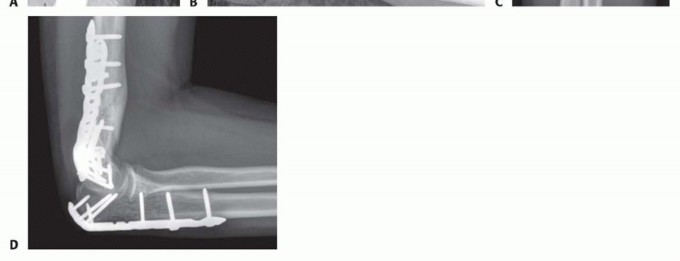

FIG 2 • A,B. A 15-year-old boy with type IIIA open distal humerus comminuted T-condylar humerus fracture. C,D. Three months following open reduction and internal fixation with olecranon osteotomy. Range of motion 0 to 140 degrees with no pain. Older children and young adolescents will often require an open approach. Comminution in the fossa may necessitate an olecranon osteotomy (FIG 2).Generally, pediatric fractures are less comminuted than adult fractures and may not require a full osteotomy.A Morrey slide approach is used in such a case where the triceps and ulnar periosteum are elevated off the ulna medially to expose the distal humerus without performing an osteotomy.3It was originally described to avoid olecranon osteotomies in cases where total elbow replacement would be a salvage operation.It can be useful in adolescents because the fractures are not as comminuted, but excellent visualization of the joint is desirable to provide anatomic reduction and restoration of elbow function. FIG 3 • A. A 13-year-old boy with a T-condylar humerus fracture with coronal split of the capitellum. B.